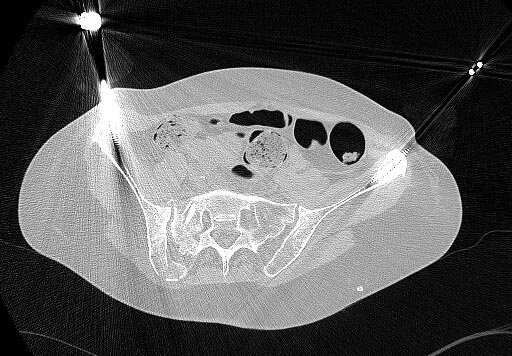

Женщина 51 год, травма в ДТП. Неврология незначительна справа, заключается в иррадиации болей по задней поверхности бедра. Движения в суставах правой нижней конечности не ограниченны.Но картина КТ заставляет задуматься? Что посоветуете?